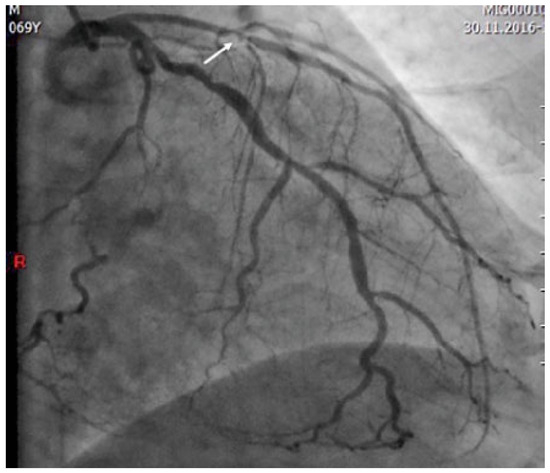

Vor über 200 Jahren hat William Heberden als Erster die typischen Beschwerden der Angina pectoris beschrieben und auch auf die Gefährlichkeit der Erkrankung hingewiesen (Abb. 1) [...]